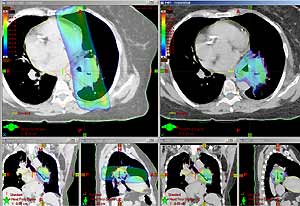

IMRT technology allows radiation oncologists to sculpt the edges of the tumor and match the radiation beam to the exact shape of the tumor. This delivers a precise dose of radiation while reducing the damage to adjacent healthy tissue and side effects.

RapidArc radiotherapy technology is a fast and precise form of IMRT that delivers more radiation to the tumor and potentially less to surrounding healthy tissue. RapidArc treatment uses a single 360° rotation of the linear accelerator, which takes less than five minutes.